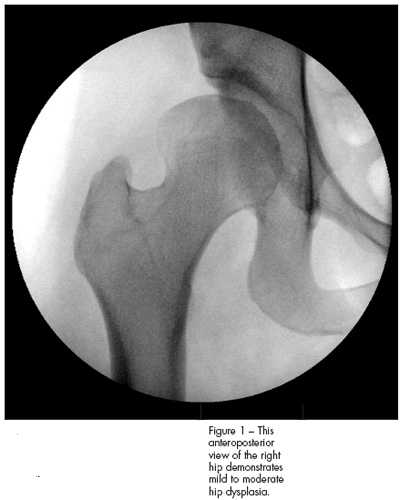

Radiographs were obtained. A standing anteroposterior (AP) view of the pelvis and bilateral false profile (25 degrees oblique) views of the hips revealed a dysplastic hip on the right side with mild coxa magna (slightly large femoral head compared with the left side) (Figure 1). The lateral center edge angle of the right hip was neutral, and the anterior center edge measured −5 degrees. Anterior and lateral coverage of the left hip, by contrast, was more than 25 degrees (which is the norm). There was minimal subluxation, and congruency between the femoral head and the acetabulum was maintained on radiography.